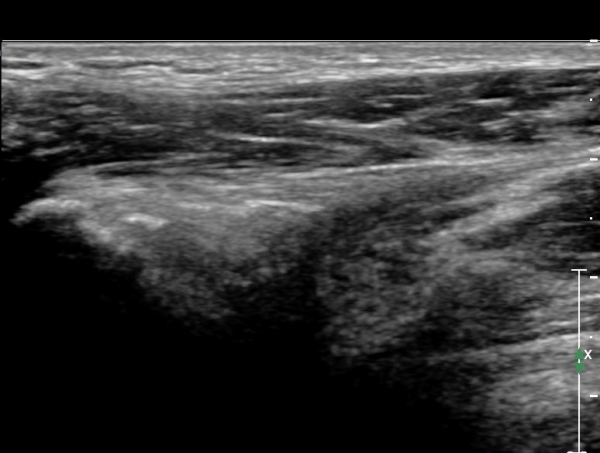

ÃÊÀ½ÆÄ°Ë»ç: °í°üÀý ¾ÕÂÊ Á¾´Ü¸é °Ë»ç¿¡¼­ °üÀý³¶ÀÌ µÎ²¨¿öÁö°í °æ¹ÌÇÑ °üÀý³» ºÎÁ¾À» º¸ÀÓ(»çÁø1, 2)